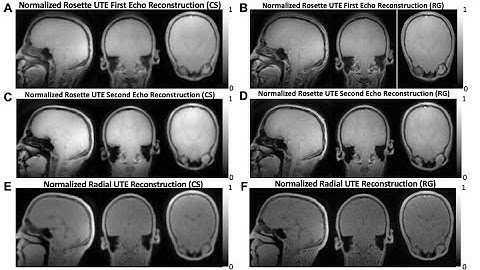

3D Dual-echo Ultra-short Echo Time MRI with Rosette k-Space Pattern